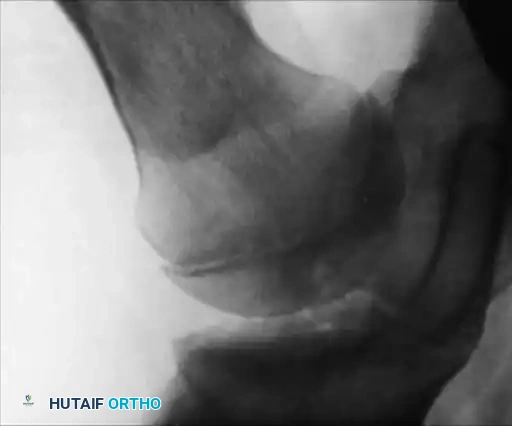

Image

Fig. 29-35: Damaged knee joint with hemophilia (factor VIII deficiency). Note the marked destruction and erosion of the articular surface of the femoral condyle, gross erosion of the tibial plateaus, and complete destruction of the menisci by invasive hypertrophic synovium.